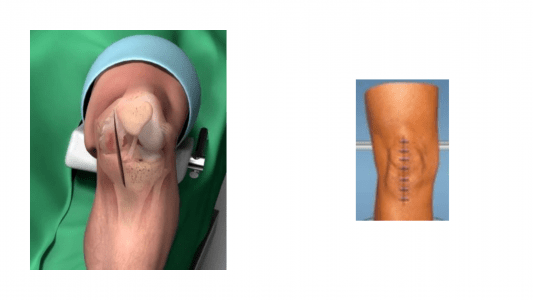

- Μικρότερη τομή και χειρουργική προσπέλαση (Εικόνα 3),